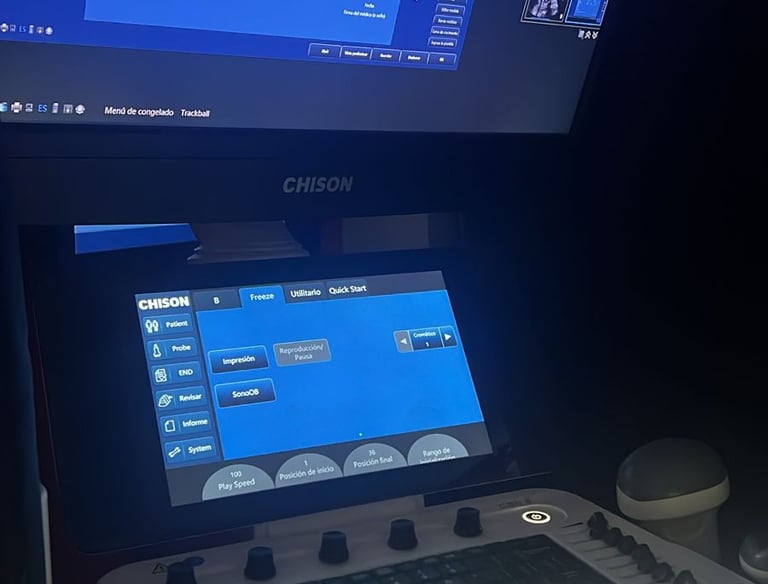

Ultrasonidos especializados realizados por el DR. Irving Gutierrez Camacho

Ultrasonidos en general.